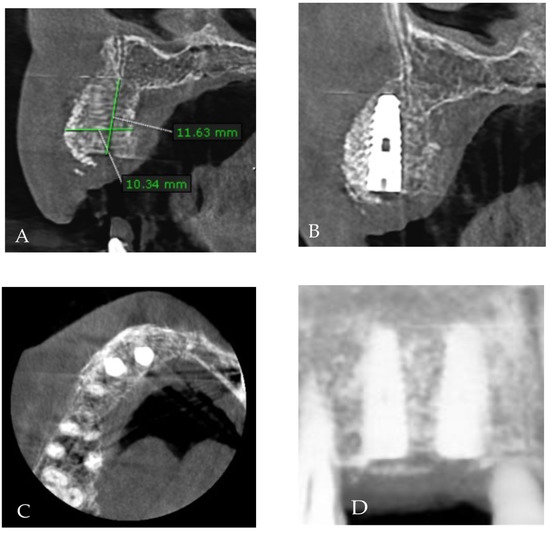

2. Case Presentation